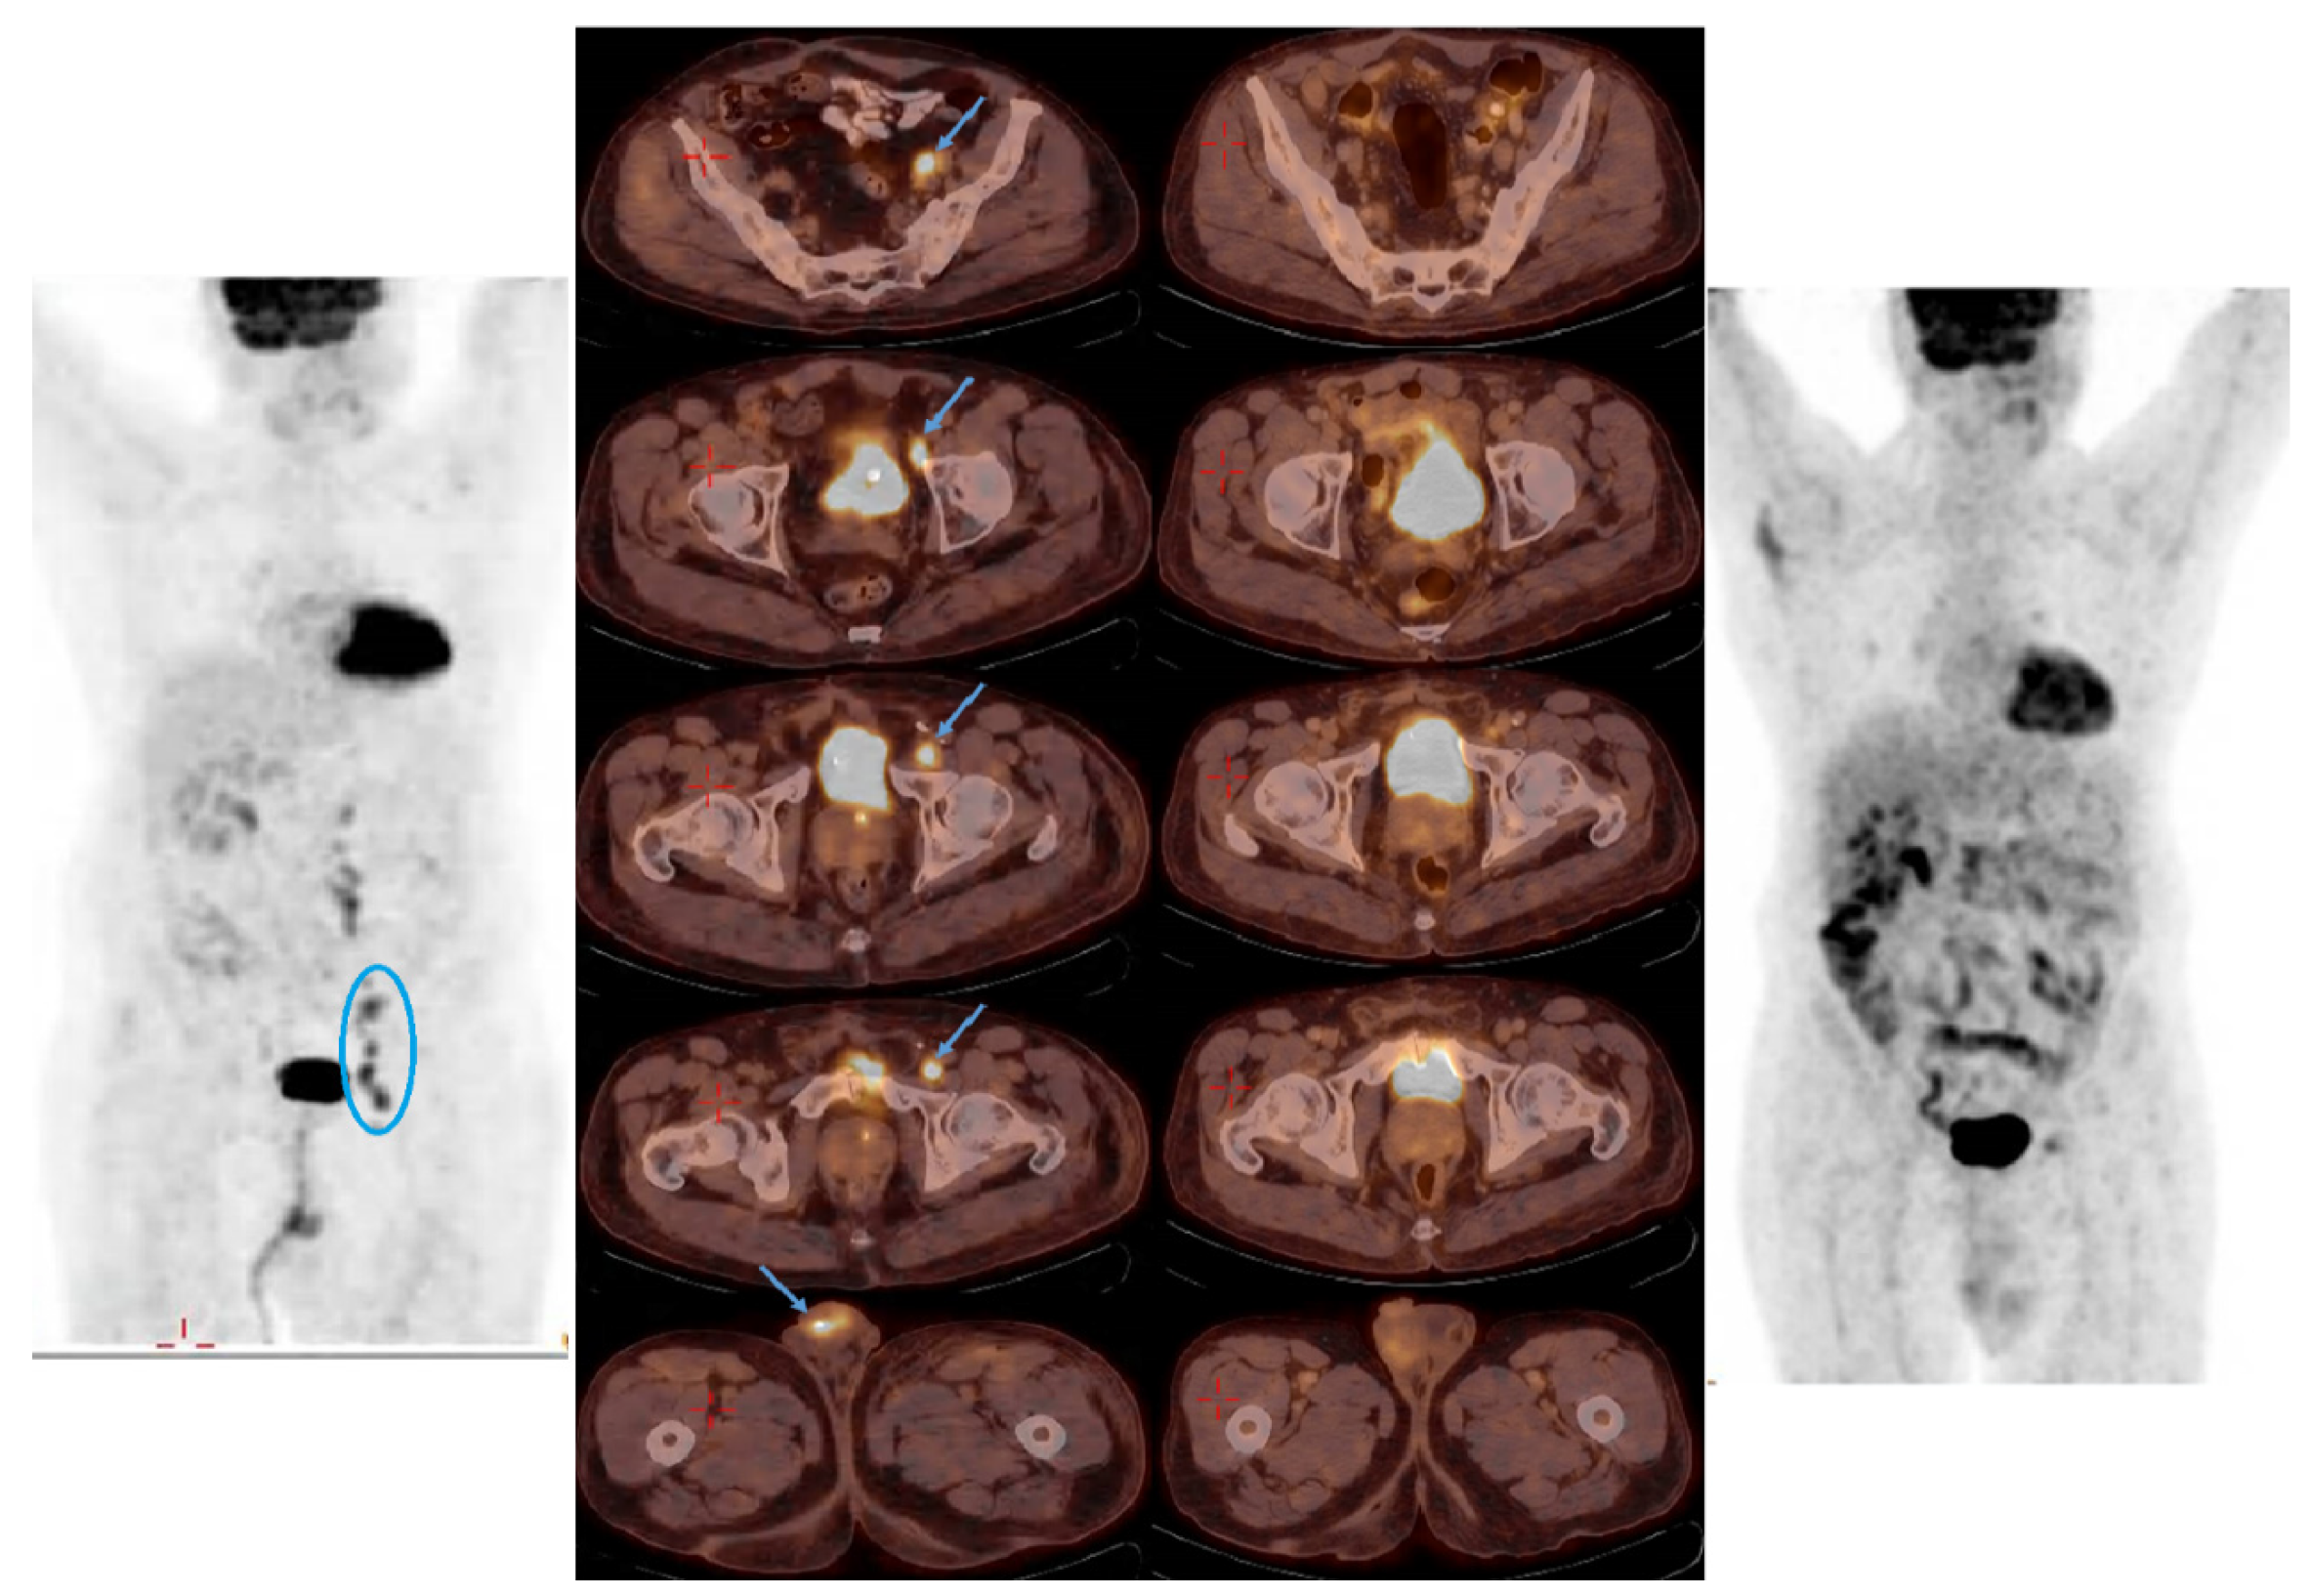

3.1. Elderly Patient with a Chronic Renal Failure

3.2. Eligible for Cisplatin but Refusing Surgery and Chemotherapy

3.3. Chronic Renal Failure with Extensive Disease